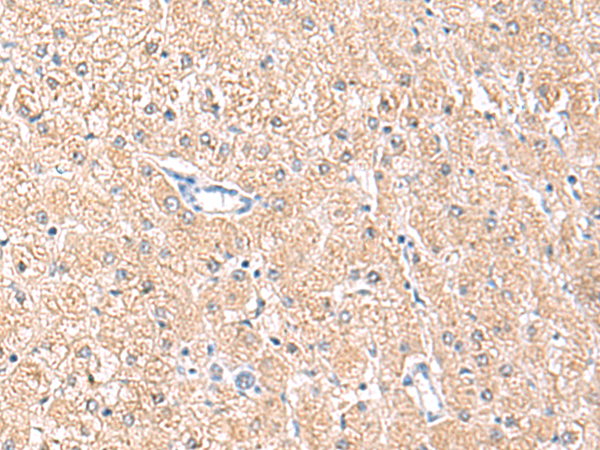

分类: 科研抗体货号: P10044别名: ARL6; ARF4L应用: IHC反应种属: Human, Mouse